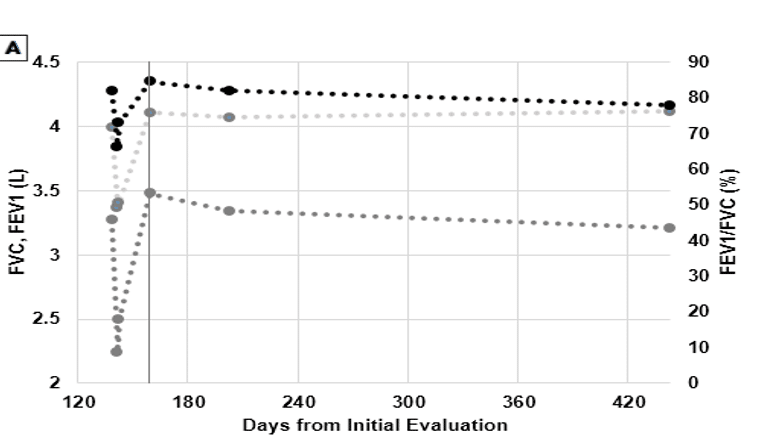

Correlation of Serial IgE and Spirometry in a Case of Baker’s Asthma

Occupational and baker’s asthma are well-understood forms of airway restriction and hypersensitivity. Serum immunoglobulin E (IgE) monitoring is often recommended...Read More